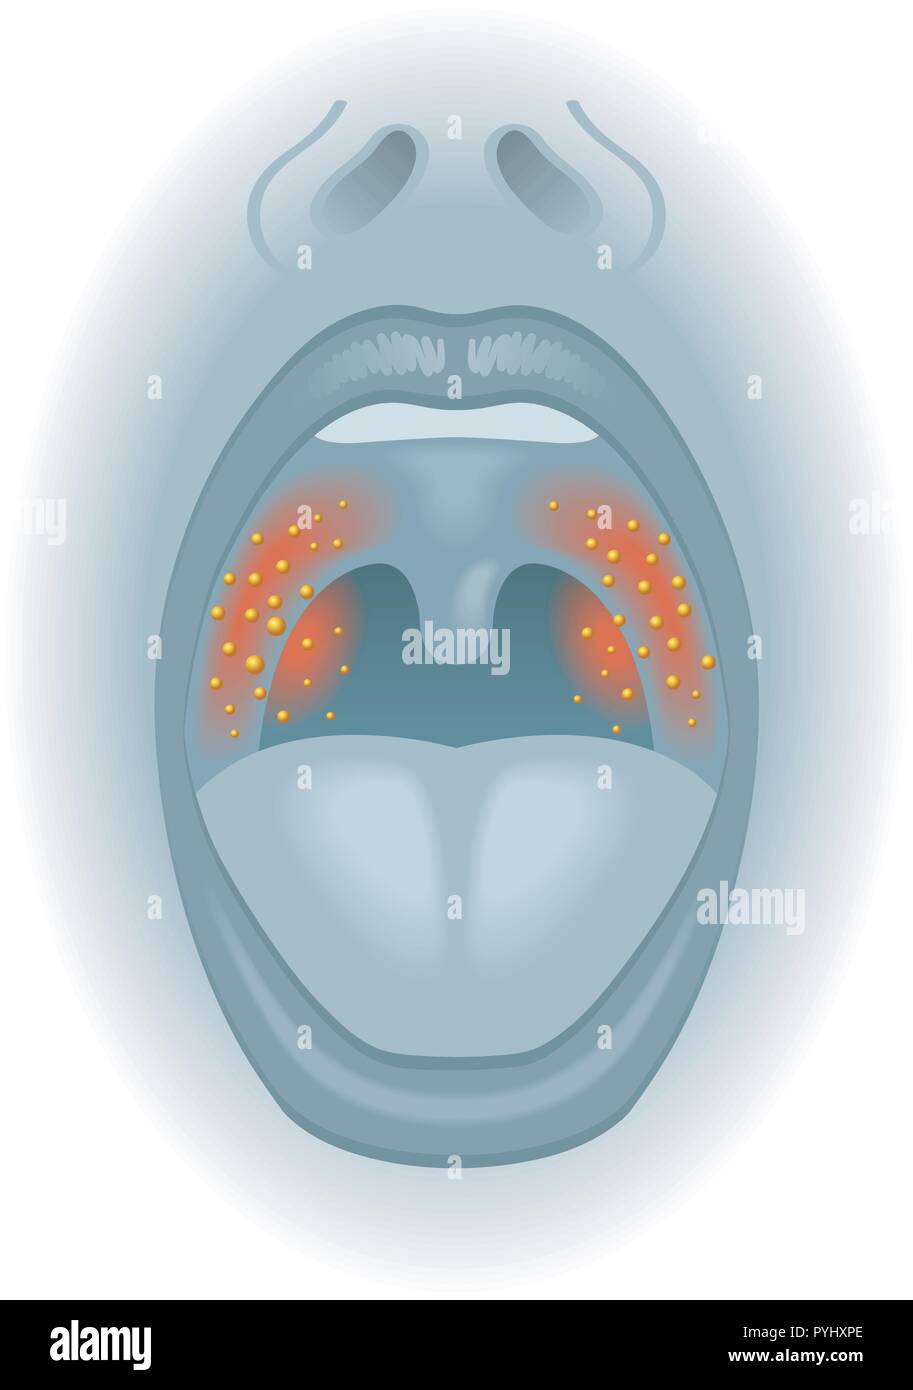

Medizinische Illustration der Auswirkungen von Halsschmerzen Stock Vektorhttps://www.alamy.de/image-license-details/?v=1https://www.alamy.de/medizinische-illustration-der-auswirkungen-von-halsschmerzen-image223514326.html

Medizinische Illustration der Auswirkungen von Halsschmerzen Stock Vektorhttps://www.alamy.de/image-license-details/?v=1https://www.alamy.de/medizinische-illustration-der-auswirkungen-von-halsschmerzen-image223514326.htmlRFPYHXPE–Medizinische Illustration der Auswirkungen von Halsschmerzen